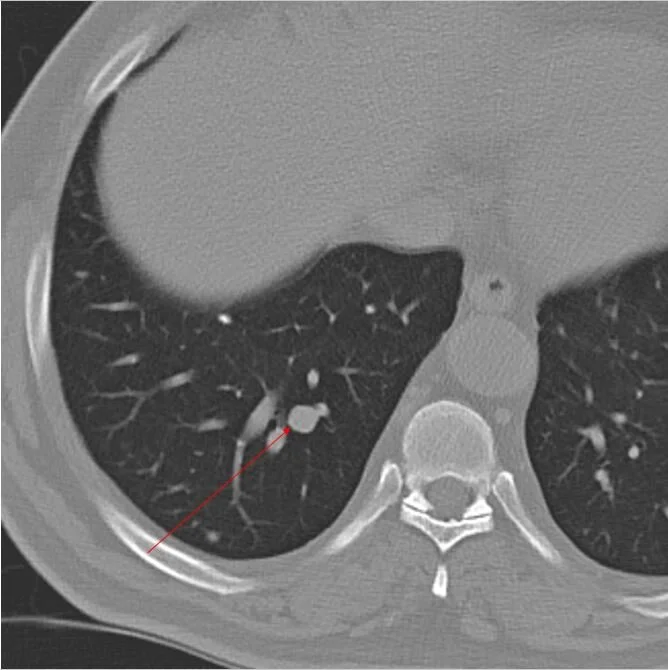

CT 2 years after nephrectomy. Tint RLL lung nodule.

Followup CT 1 year later, nodule is larger. This was oligometastasic disease.